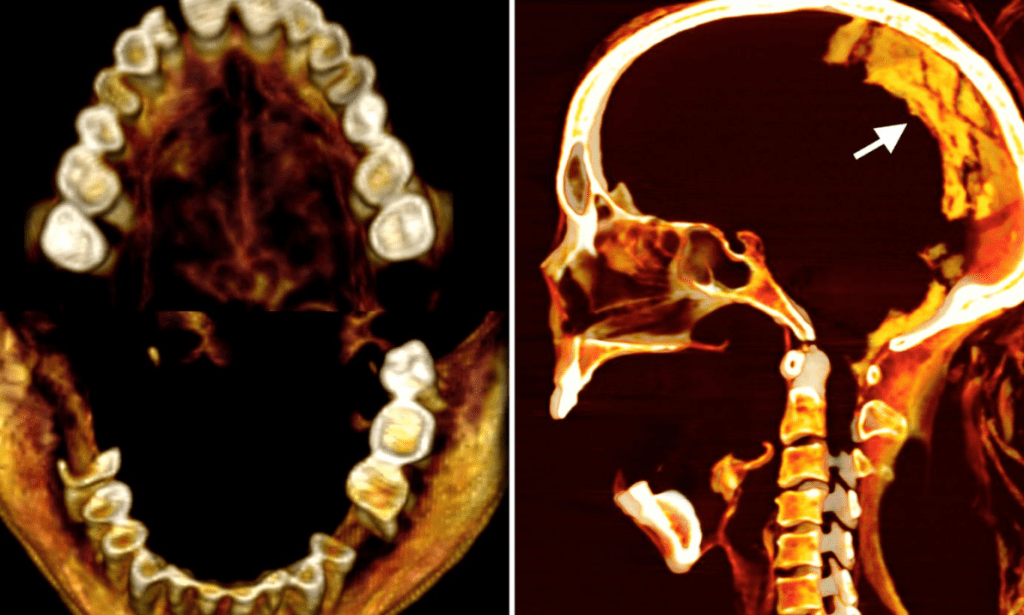

Today, scientists decided to unravel the mystery. They used CT scans to perform a “virtual dissection” to uncover the truth behind her agonizing expression. They also relied on infrared imaging and other advanced techniques to shed more information about the mummy.

Along with the reason behind her shocking face, Cairo University radiology professor Sahar Saleem, the scientist leading the study, also discovered that the mummy was 48 years old when she died, that she had lived with mild arthritis of the spine, and that she had lost some teeth.

When it comes to her mummification process, Saleem noticed how it was pretty unusual. He found that she had no incisions in her body and that her brain, diaphragm, heart, lungs, liver, spleen, kidneys, and intestines were all still in her body.